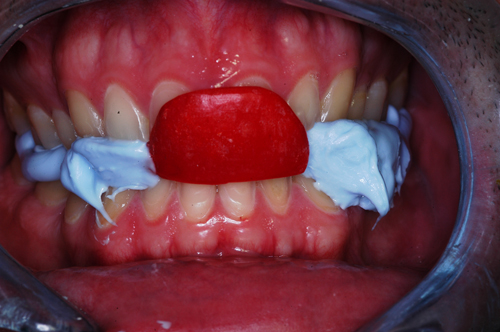

REHABILITACION ORAL MEDIANTE CORONAS DE PORCELANA DE ALTA DENSIDAD Protocolo D.A.T.O. CASO CLINICO: Paciente 24 años, bruxómano, atresia maxilar, referido por ortodoncista para realizar rehabilitación oclusal . Se observa a la inspección la presencia de una hipoplasia adamantina en todos los dientes anteriores, carencia de Guía Anterior , evidentes signos de Facetas Parafuncionales de Desgaste en los posteriores, y una marcada convergencia de los ejes dentarios ápico oclusal, tanto en el maxilar superior como en el inferior, siendo el superior el mas difícil de resolver dado que la inclinación de la Curva de Wilson es inversa a lo que presenta el enfermo. Radiograficamente sin patologías presentes. No presenta movilidades dentarias ni síntomas articulares en las ATM. Debido a la excesiva contractura de su musculatura, se realiza la relajación obviando el uso corriente de las Laminillas de Long, reemplazando el método por un Jig de Lucia el que se deja en boca desde la noche anterior a la cita, advirtiendo al paciente que no debe quitarlo en ningún momento , ya que de hacerlo se repetirían los engramas musculares anómalos que el enfermo presenta. En esas condiciones se toman registros intermaxilares mediante silicona de registros, y se registra el maxilar superior respecto del plano de Frankfort mediante arco facial estático. Se llevan a cabo los encerados correspondientes y se construye en base a ellos el primer juego de provisionales, los que no son cementados debido al perfecto anclaje que presenta. Transcurridos seis meses del uso de provisionales , durante los cuales se ha observado la Oclusión en Relación Céntrica (ORC) inalterable, la ausencia de desgastes patológicos (en las provisorias) y la ausencia de síntomas articulares y musculares, deducimos que el paciente se mantiene en una orto función adecuada, por lo cual comenzamos su rehabilitación definitiva construyendo su Guía Anterior ( determinante primario de la oclusión) en porcelana sobre porcelana de alta densidad.. Observamos los espacios correspondientes en los sectores posteriores y las Disclusiones de los mismos. Los tallados ha sido realizados mediante el concepto de Tallados Gnatológicos, recreados por el Prof. Alvarez Cantoni bajo la denominación de “Preparaciones Racionales”( PREPARACIONES RACIONALES EN PRÓTESIS PARCIAL FIJA. Ed. Hacheace) probando finalmente el trabajo luego de varios días de cementado provisional, y observando la adaptación periférica del borde cavo superficial , su aspecto estético y el importante factor disclusivo : CURVA DE WILSON. y verificando la eficacia lograda mediante una Oclusión Mutuamente Compartida, en la observación de una Disclusión derecha en el Lado de Trabajo y no Trabajo de una disclusión izquierda como así también en la disclusión propulsiva Utilizamos papel de articular de ocho(8) micras para verificar la eficacia de las disclusiones. y de los puntos interoclusales de contacto ANTES DESPUES

Se instalan en cambio con una crema dermatológica a base de corticoides, lo que nos provee de un antinflamatorio de contacto excelente para posteriores manipulaciones y confort del paciente